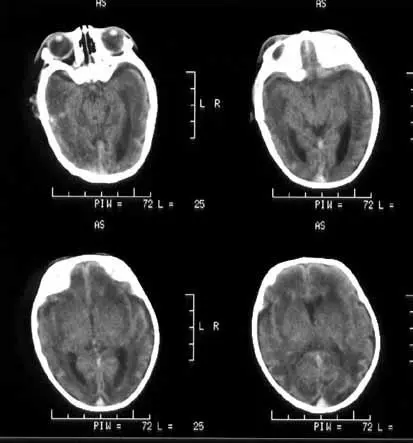

缺血缺氧性脑病(简称HIE)是由多种原因导致的脑缺血、缺氧最终引发脑神经系统损伤的疾病,常见于新生儿中。

据统计,全球范围内约有115万婴儿患有HIE,大约每1000个新生儿中就有1.5名患有该病,这其中,高达25%的新生儿会因HIE死亡;35%的HIE新生儿出现长期神经发育后遗症。